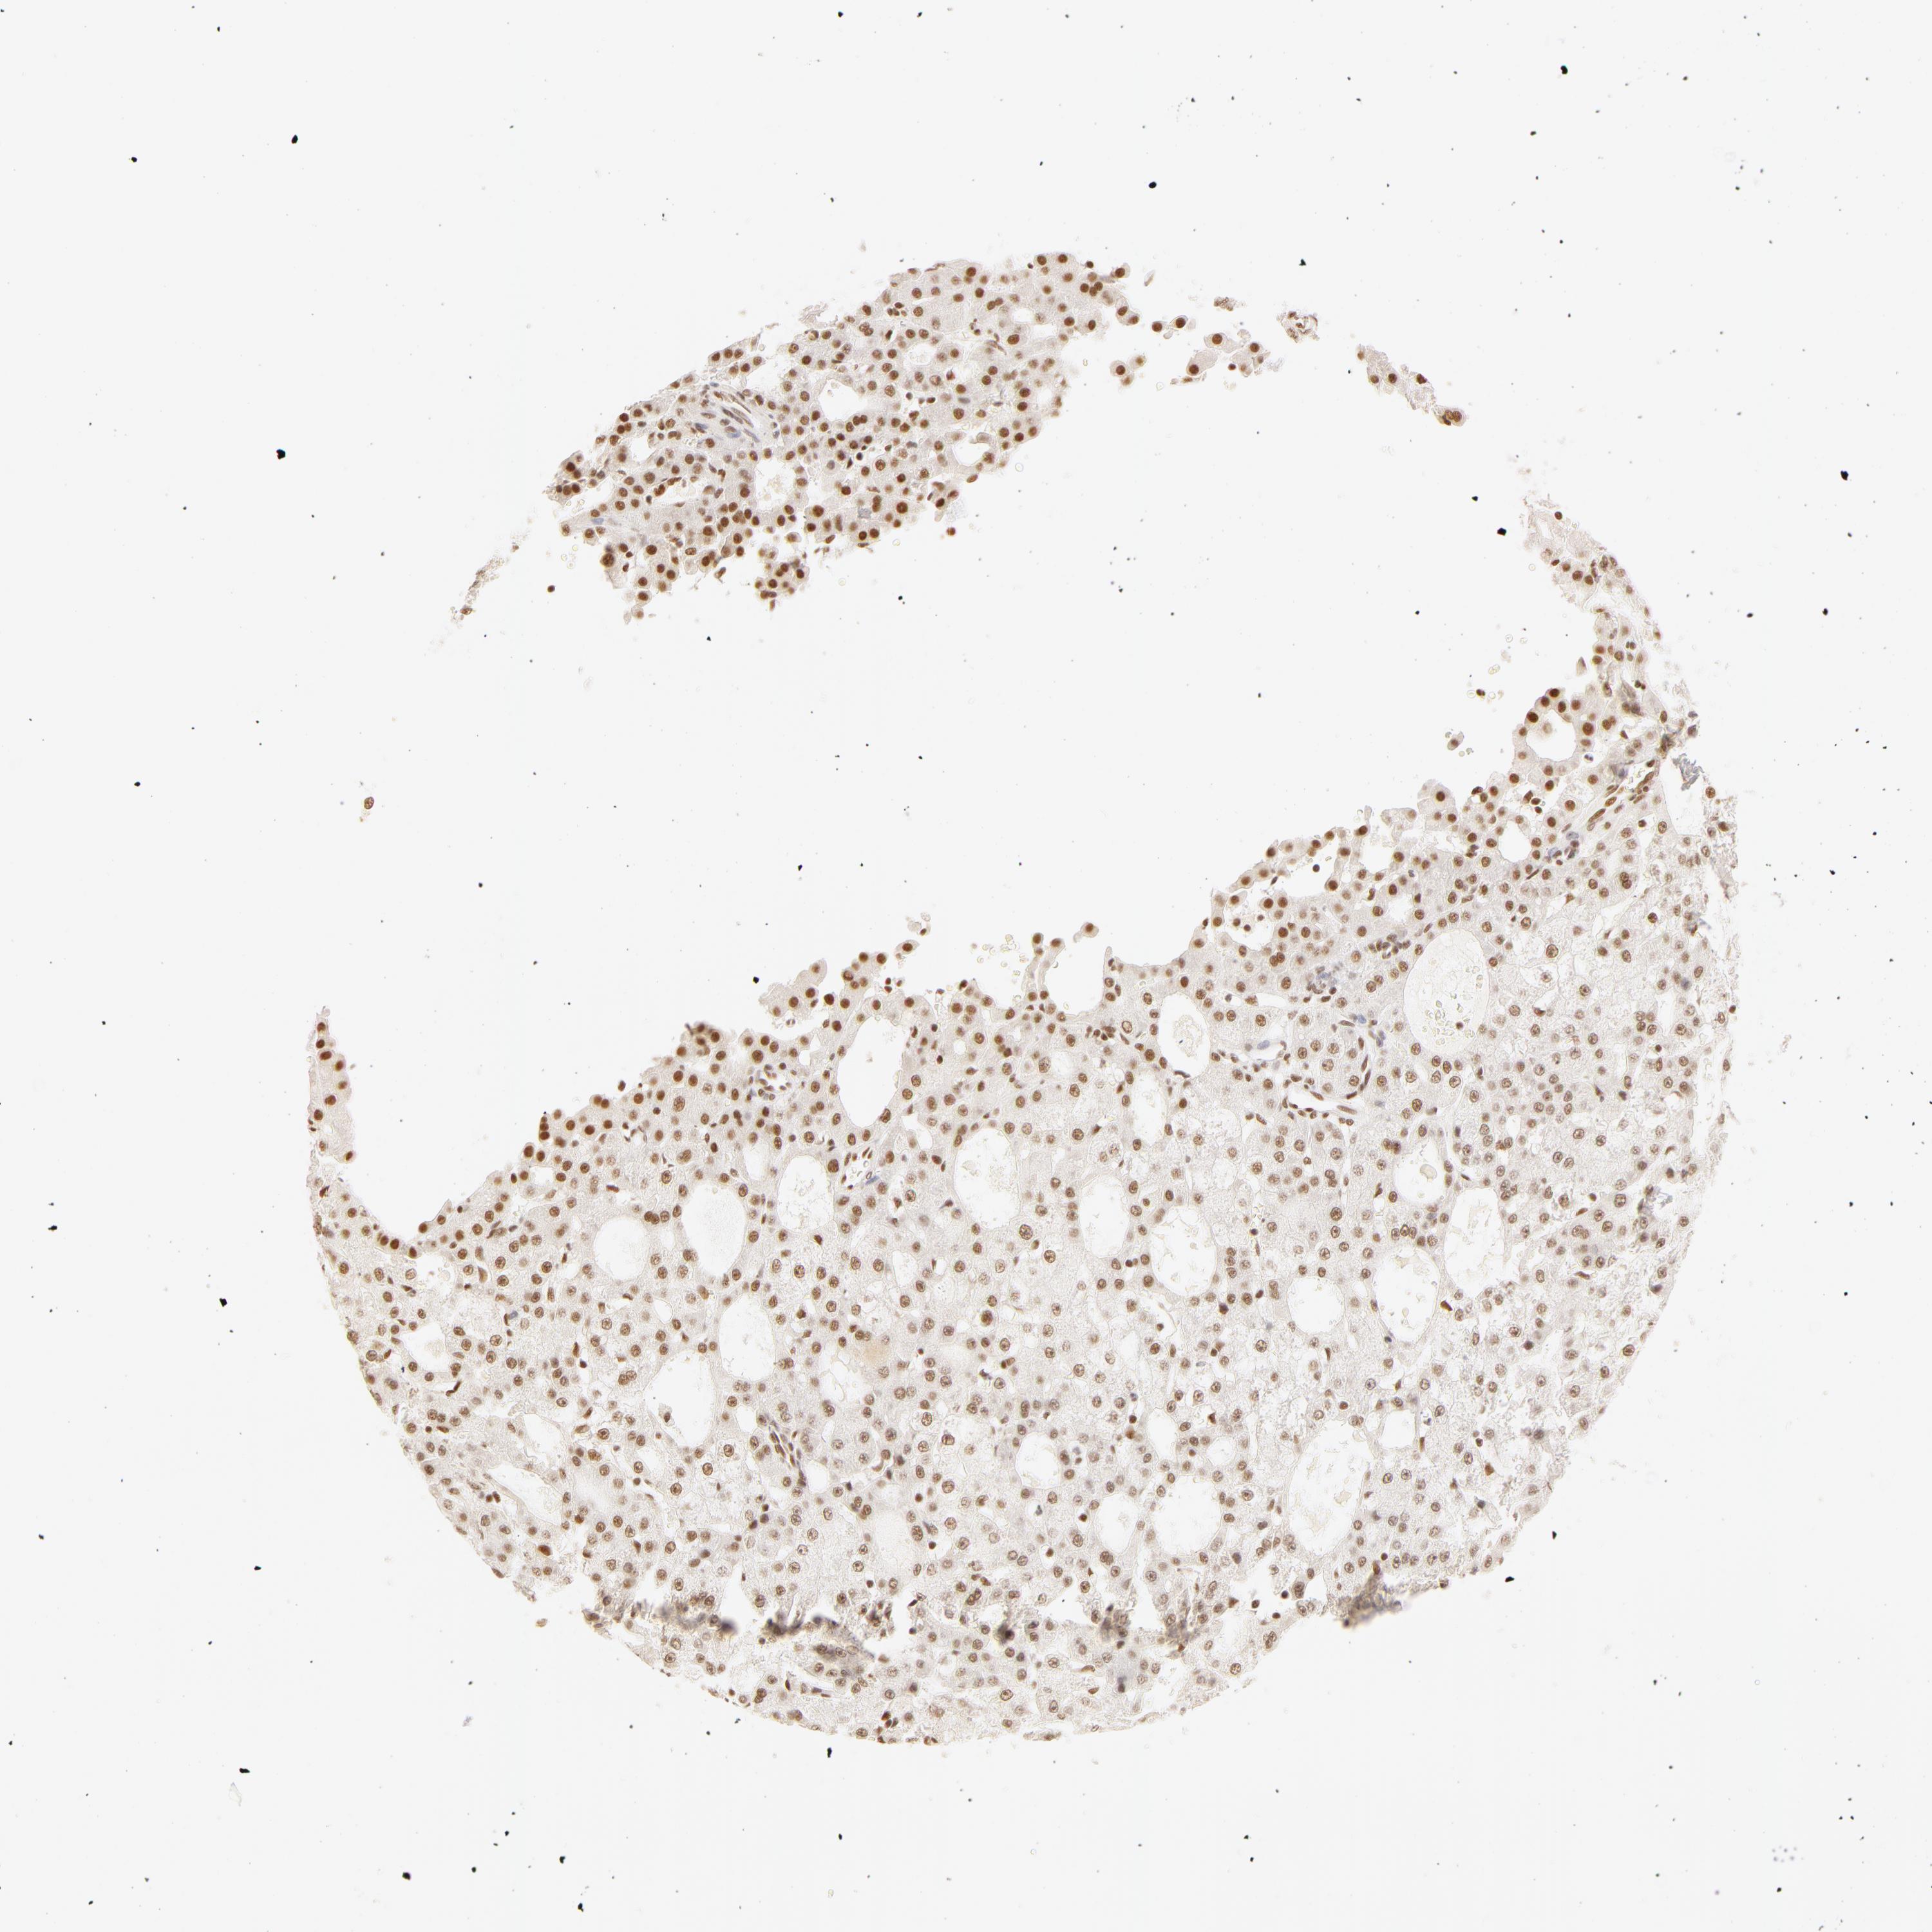

LIVER CANCER - Protein expressioni

A mouse-over function shows sample information and annotation data. Click on an image to view it in a full screen mode. Samples can be filtered based on level of antibody staining by selecting one or several of the following categories: high, medium, low and not detected. The assay and annotation is described here.

Note that samples used for immunohistochemistry by the Human Protein Atlas do not correspond to samples in the TCGA dataset.

Antibody stainingi

Antibody staining in the annotated cell types in the current human tissue is reported as not detected, low, medium, or high, based on conventional immunohistochemistry profiling in selected tissues. This score is based on the combination of the staining intensity and fraction of stained cells.

Each image is clickable and will lead to virtual microscopy that enables deeper exploration of all samples and also displays staining intensity scores, fraction scores and subcellular localization as well as patient and tissue information for each sample.

Antibody HPA001591

Staining

High

Medium

Low

Not detected

Intensity

Strong

Moderate

Weak

Negative

Quantity

>75%

75%-25%

<25%

None

Location

Nuclear

Cytoplasmic/membranous

Cytoplasmic/membranous,nuclear

Cholangiocarcinoma